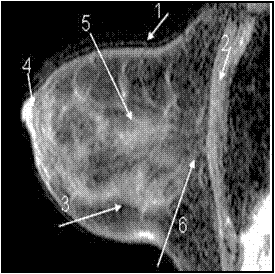

На основании оценки полученных данных установлено, что на МР- маммограммах визуализируются все основные анатомические структуры МЖ, представляющие клинический интерес (рис. 22).

Рисунок 22 — МР-маммограмма нормальной МЖ.

1 — кожа;; 2 — грудная мышца;; 3 — жировая ткань;; 4 — сосок;; 5 — железистая ткань;; 6 — ретромаммарное пространство.